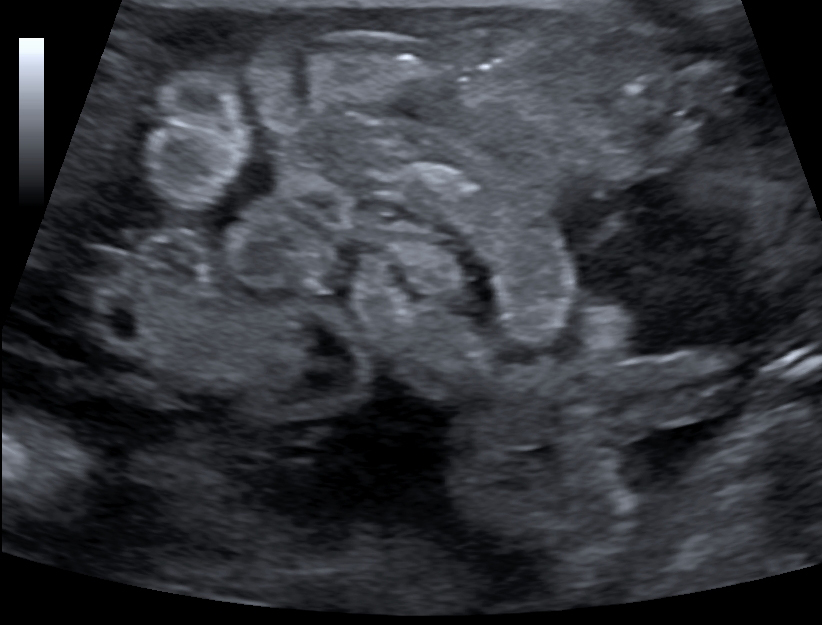

La enterocolitis necrosante (NEC) es una condición grave en neonatos, especialmente en aquellos prematuros, y la ecografía abdominal se ha convertido en una herramienta valiosa para su diagnóstico y manejo. Los hallazgos ecográficos en neonatos con NEC incluyen una serie de características que pueden ayudar a identificar la gravedad de la enfermedad y la necesidad de intervención quirúrgica.

1. Neumatosis intestinal: La presencia de gas en la pared intestinal es un hallazgo clásico y altamente sugestivo de NEC.

3. Engrosamiento de la pared intestinal: Un engrosamiento de la pared intestinal mayor a 2.5 mm es un hallazgo ecográfico asociado con NEC y puede ser un indicador de inflamación severa.[2][5]

4. Gas portal venoso: La presencia de gas en la vena porta es otro hallazgo ecográfico que puede estar presente en NEC, aunque su asociación con la necesidad de cirugía o muerte no es tan fuerte como otros hallazgos.[2][4]

5. Reducción del peristaltismo: La disminución o ausencia de movimiento peristáltico en el intestino es un signo de NEC y puede ser evaluado mediante ecografía.[2][4]

6. Colecciones de líquido focales y ascitis compleja: Estos hallazgos son indicativos de una posible complicación y están asociados con un mayor riesgo de requerir intervención quirúrgica.[3-4]

7. Hiperecogenicidad de los contenidos intraluminales: Este hallazgo, junto con el engrosamiento del mesenterio y las anomalías de la pared abdominal, se ha asociado con un peor pronóstico en neonatos con NEC.[6]

Estos hallazgos son cruciales para la evaluación y manejo de la NEC en neonatos, permitiendo una identificación temprana de aquellos que podrían beneficiarse de un tratamiento más agresivo, incluyendo cirugía.[4]